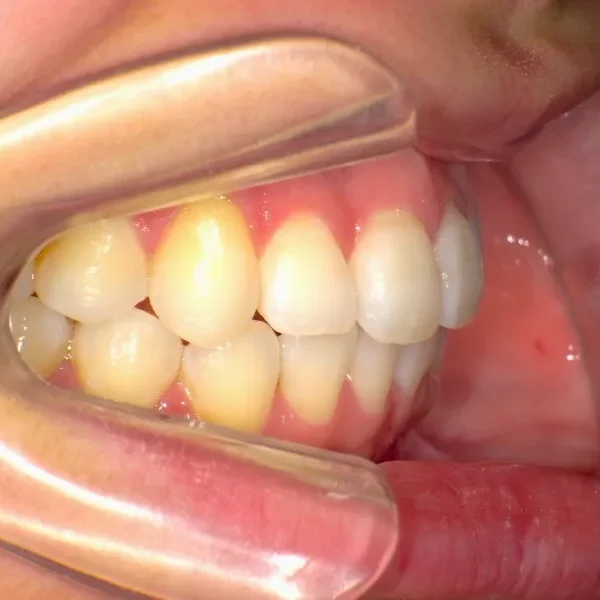

八重歯で笑うと尖った歯が目立ちます。

上下ガタガタで、下の歯は癒合歯(2本がくっついて1本の歯)です。

主訴が改善され、ご満足頂きました。